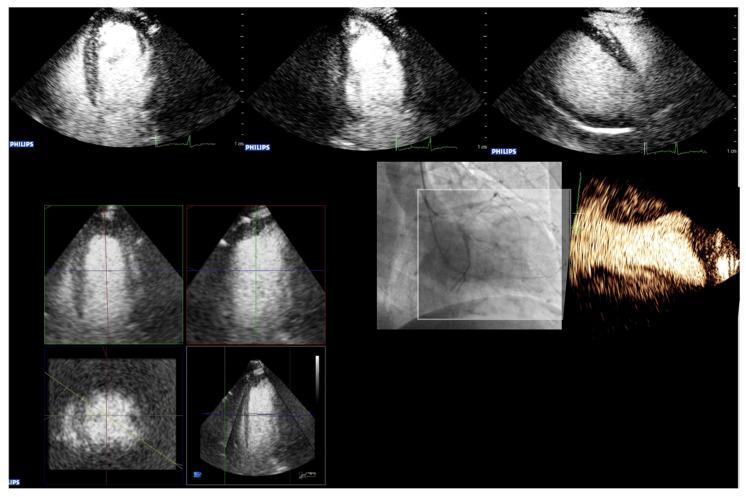

How to Perform Cardiac Contrast-Enhanced Ultrasound (cCEUS): Part I.

Ultrasound enhancing agents (UEAs, formerly called contrast agents) for assessments of the left heart have improved the applicability of echocardiography and the accuracy of echocardiographic measurements. UEAs have been recommended for several diagnostic echocardiographic procedures by national and supernational agencies. The increased use of UEAs during the last years provided more evidence and experience in clinical practice data which is helpful for optimizing the UEA procedures and which will be useful for both newcomers to UEA in echocardiography and sonographers/physicians with experience in echocardiography with UEAs. In two parts, this review focuses on the "how to do" for the approved UEA applications. This is part 1, covering the available UEAs and providing specific guidance on the assessment of global and regional LV function. Part 2 covers the imaging of myocardial disease and masses as well as myocardial perfusion. Recommendations include the application of UEAs in two-dimensional echocardiography as there is limited data on three-dimensional echocardiography. A step-by-step approach is proposed for each of the procedures as well as guidance on how to interpret recordings and how to report them.